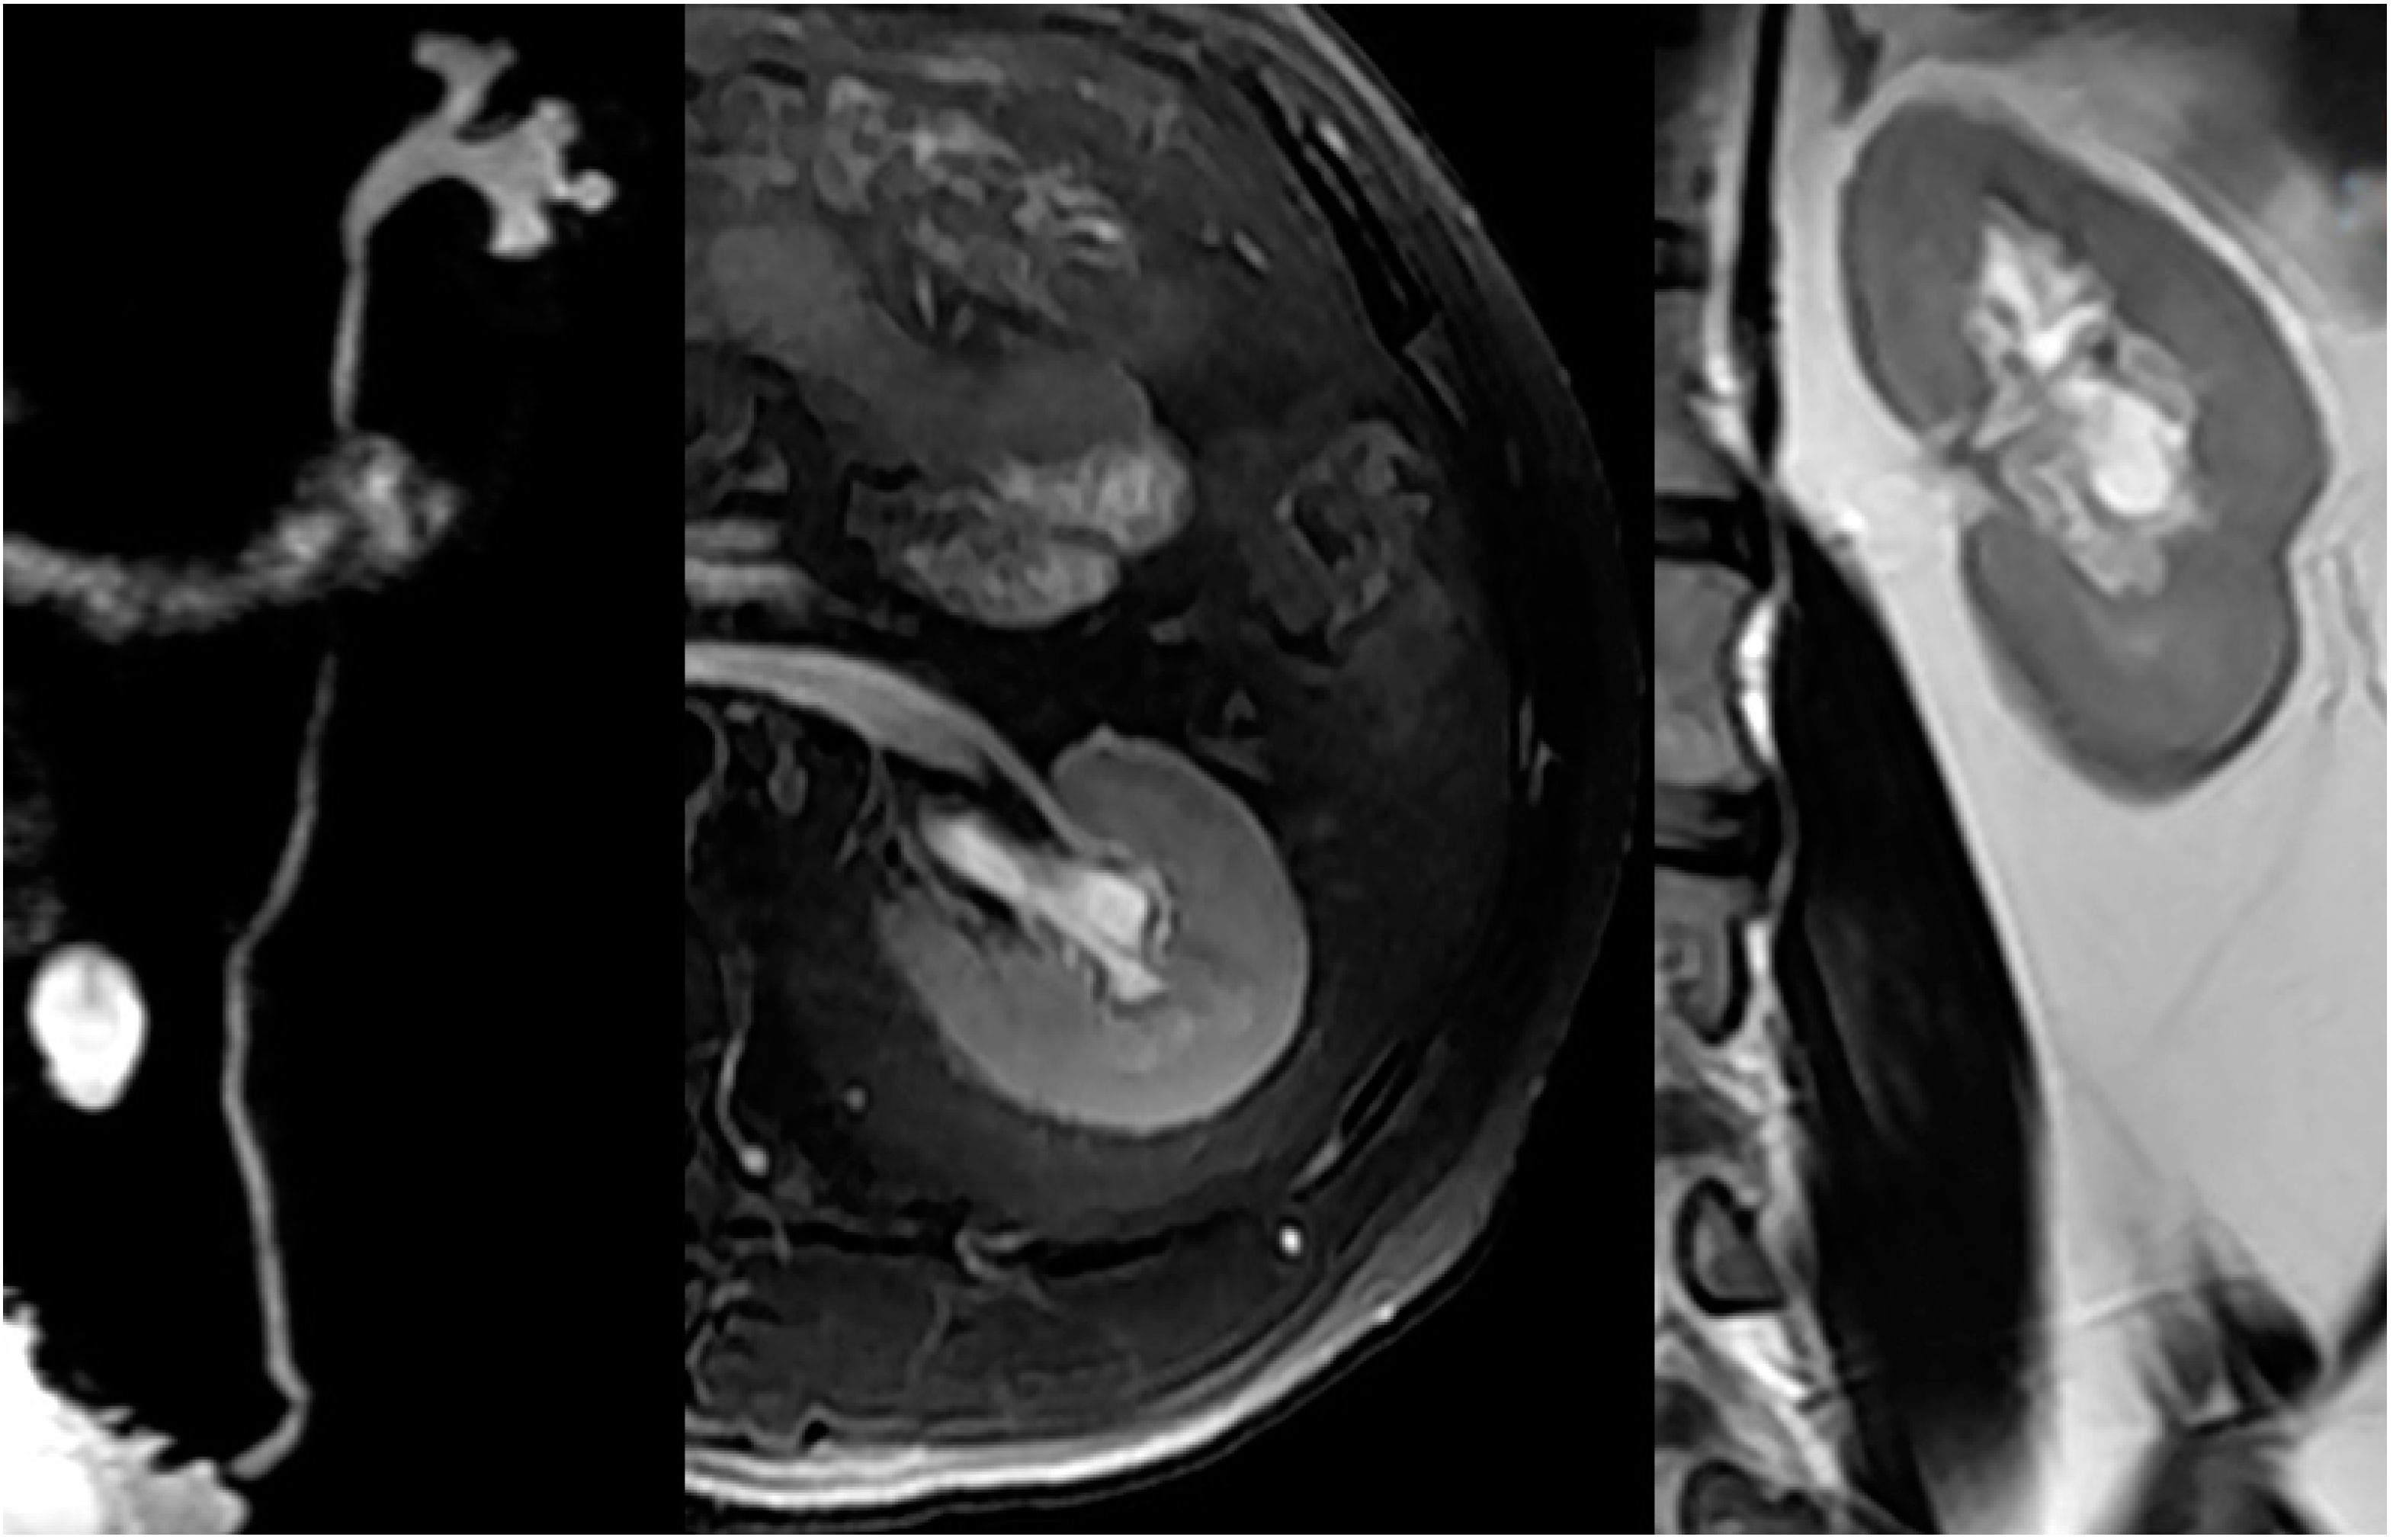

2.4. Upper Urinary Tract Imaging

2.4.1. Upper Urinary Tract Dilation (UUTD)

- Liao, L.M.; Zhang, F.; Chen, G. New grading system for upper urinary tract dilation using magnetic resonance urography in patients with neurogenic bladder. BMC Urol. 2014, 14, 38–45. [Google Scholar] [CrossRef] [PubMed]